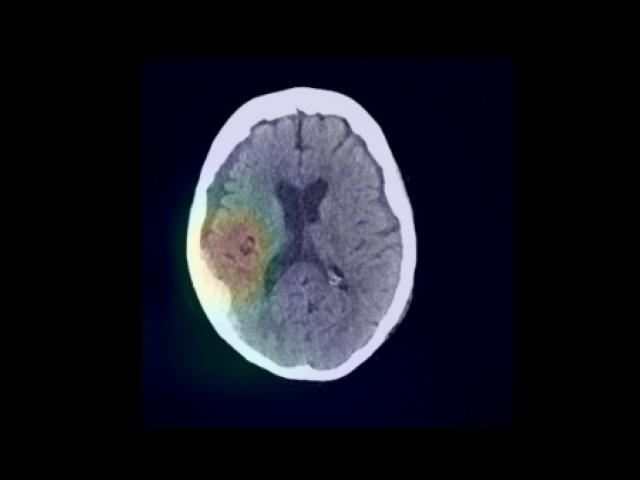

Sample Gallery